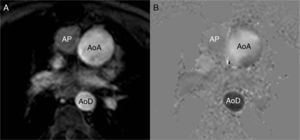

Phase contrast sequences make two different measurements, one with a bipolar gradient (of identical magnitude, on the same plane/view but in opposite directions) and the other one without this gradient. With the two packages of data and through mathematical calculations, the MRI machine determines which protons (voxels) have not changed their position (the signal is identical in the two measurements), which ones move in the same direction as the gradient (in the negative or positive direction) and how fast they move. The MRI operator must determine the direction of the flow she/he wants to measure (craniocaudal, anterior–posterior or right–left), which indicates to the machine the direction of the bipolar gradient that needs to be applied. The sequence is made contributing as a parameter the expected blood velocity in that vessel (in cm/s) that the machine calculates as gradient intensity. For an in-depth reading of the physics and the technique of this sequence we will refer the reader to specific articles.17 The MRI machine offers one package of anatomical images (of magnitude) and another package of the velocity (or phase) representing the flow in a similar way to the Doppler ultrasound (Fig. 1). Usually the flow is white in one direction and black in the other being the stationary tissue represented by a gray background and noise. It is a cyclical phenomenon that has nothing to do with the change of frequency but rather with the phase. Thus parameters need to be adjusted to the flow velocity to be studied, since it experiences aliasing artifacts if velocity is higher than expected and curves with not enough data (noise) if velocity is lower (Fig. 2).